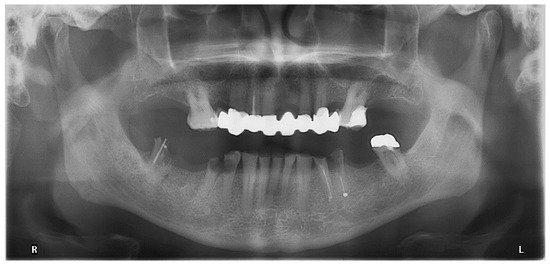

- Locator abutments on both implants, single-crown FDPs on the remaining lower molar teeth, insertion of a tooth-colored and tooth-shaped monolithic RDP fabricated from POM with minimally invasive preparation of the lower anterior teeth (experimental character in long-term endurance).